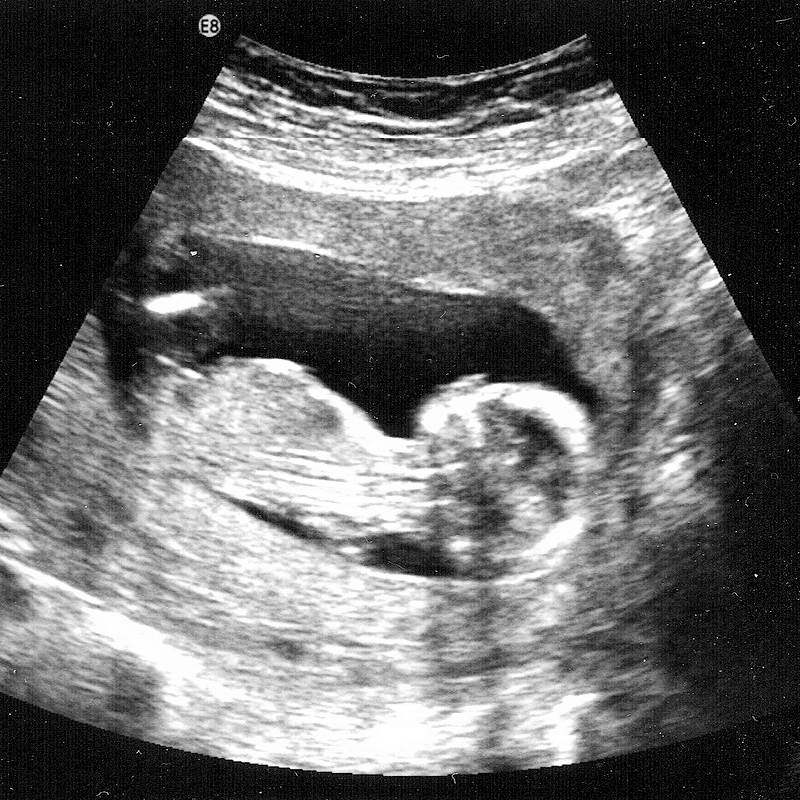

wallpaper 14 Weeks Pregnant Pregnancy

2011 14 weeks

2010 Week 14 gt; 14 weeks

hair pregnancy photo 14 weeks

hot 14 weeks pregnant

house Celine Dion is now 14 weeks

tattoo 9 weeks pregnant.

pictures 14 weeks pregnant. I#39;m 14 weeks pregnant and was

dresses 14 weeks pregnant. 14 weeks; 14 weeks. kainjow. Apr 18, 10:46 PM

girlfriend 1st Baby, 14 Weeks

hairstyles 14+weeks+pregnant+scan